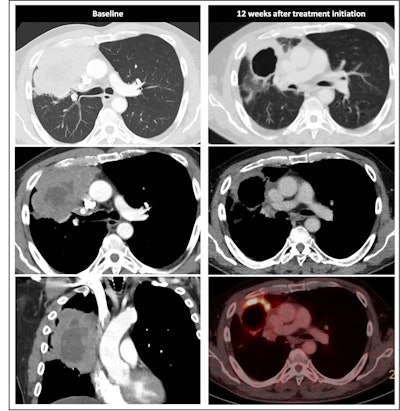

Radiological response inconsistent with pathological response: 69-year-old patient with non-small cell lung cancer (NSCLC) received a neoadjuvant treatment with three cycles of immune-checkpoint inhibitor therapy plus chemotherapy (ICIT + C, carboplatin/pemetrexed/pembrolizumab). 12 weeks after treatment began, the patient showed complete pathologic response (ypTo, pNo) but only partial radiological response.

The researchers noted in a poster presentation at RSNA in Chicago that a minority of patients with cPR show complete radiological response (24% vs. 1.1%). Also, ICIT leads to inflammatory cell infiltration with edema and later on tumor cell necrosis or fibrosis, the authors continued. Initially, this may lead to no change in lesion size, increase or appearance of new lesions (pseudoprogression), and mimicking of residual disease.

Most patients will have a residual tumor and fibrotic tissue, leading to insufficient assessment with standard-of-care imaging, while major pathologic response involves a reduction in tumor size with residual tissue and no major pathologic response means a reduction in tumor size or stable disease.